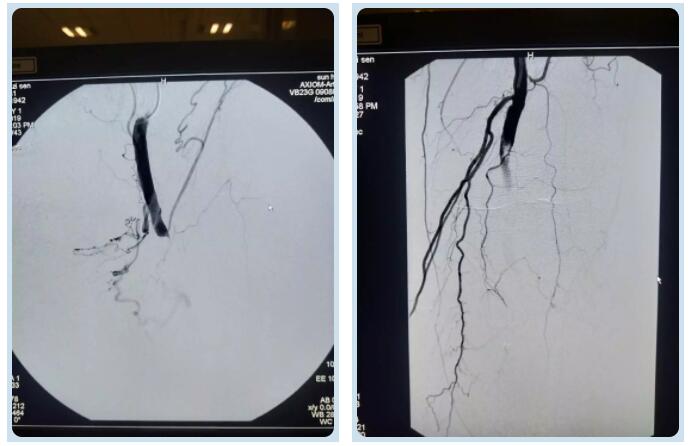

股總動(dòng)脈及腘動(dòng)脈堵塞處

股總動(dòng)脈及腘動(dòng)脈取栓后

劉主任抵達(dá)醫(yī)院后,快速為王大爺制定了周密的介入方案,經(jīng)過完善的術(shù)前準(zhǔn)備,劉主任帶領(lǐng)團(tuán)隊(duì)為王大爺進(jìn)行介入手術(shù)。經(jīng)動(dòng)脈造影,發(fā)現(xiàn)王大爺下肢大血管有兩處動(dòng)脈血栓,分別在大腿根部及膝關(guān)節(jié)部位,情況十分危急。劉綿春主任決定立即為患者實(shí)施股總動(dòng)脈及腘動(dòng)脈取栓術(shù)。介入科醫(yī)師們利用動(dòng)脈穿刺技術(shù)及導(dǎo)管技術(shù),將直徑2.6mm的導(dǎo)管插入血栓位置進(jìn)行吸取。30分鐘、60分鐘、90分鐘……時(shí)間在一分一秒中度過?!按笸雀咳∷ǔ晒Γ中g(shù)完成一半!”劉主任的聲音里帶著一絲絲喜悅,同時(shí)叮囑身旁的同事不能有一絲懈怠,顧不及早已被汗水浸濕的手術(shù)衣,也顧不及疲憊不堪的身體,劉綿春主任和他的團(tuán)隊(duì)繼續(xù)進(jìn)行著介入手術(shù)。凌晨一點(diǎn)十五分,再次造影顯示右腿恢復(fù)血流,經(jīng)過醫(yī)護(hù)人員的共同努力、密切配合下,歷時(shí)三個(gè)半小時(shí),這場(chǎng)微創(chuàng)手術(shù)終于以成功告終。王大爺冰涼、紫紺的腿恢復(fù)了溫暖和紅潤(rùn),效果可謂立竿見影,而且沒有留下傷痕,讓患者及家屬感到十分欣喜。術(shù)后,患者被送往骨外科病房,經(jīng)過醫(yī)護(hù)人員精心護(hù)理和治療患者已下床活動(dòng)。